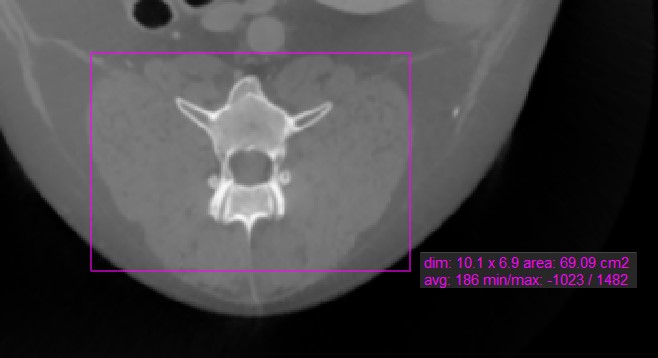

Rectangle

../_images/image96.jpg

The Rectangle tool offers users the ability to mark a rectangular area on the active image slice.

Select the Rectangle tool and assign it to one of the available mouse buttons. Start the measurement by pressing on the active image slice and drag the mouse to obtain a rectangular shape. Release the mouse when satisfied with the size of the marked area.

All available measurement values are displayed alongside the measurement.

Modify the marked area by moving one of the four points of the rectangular shape using the Default tool.